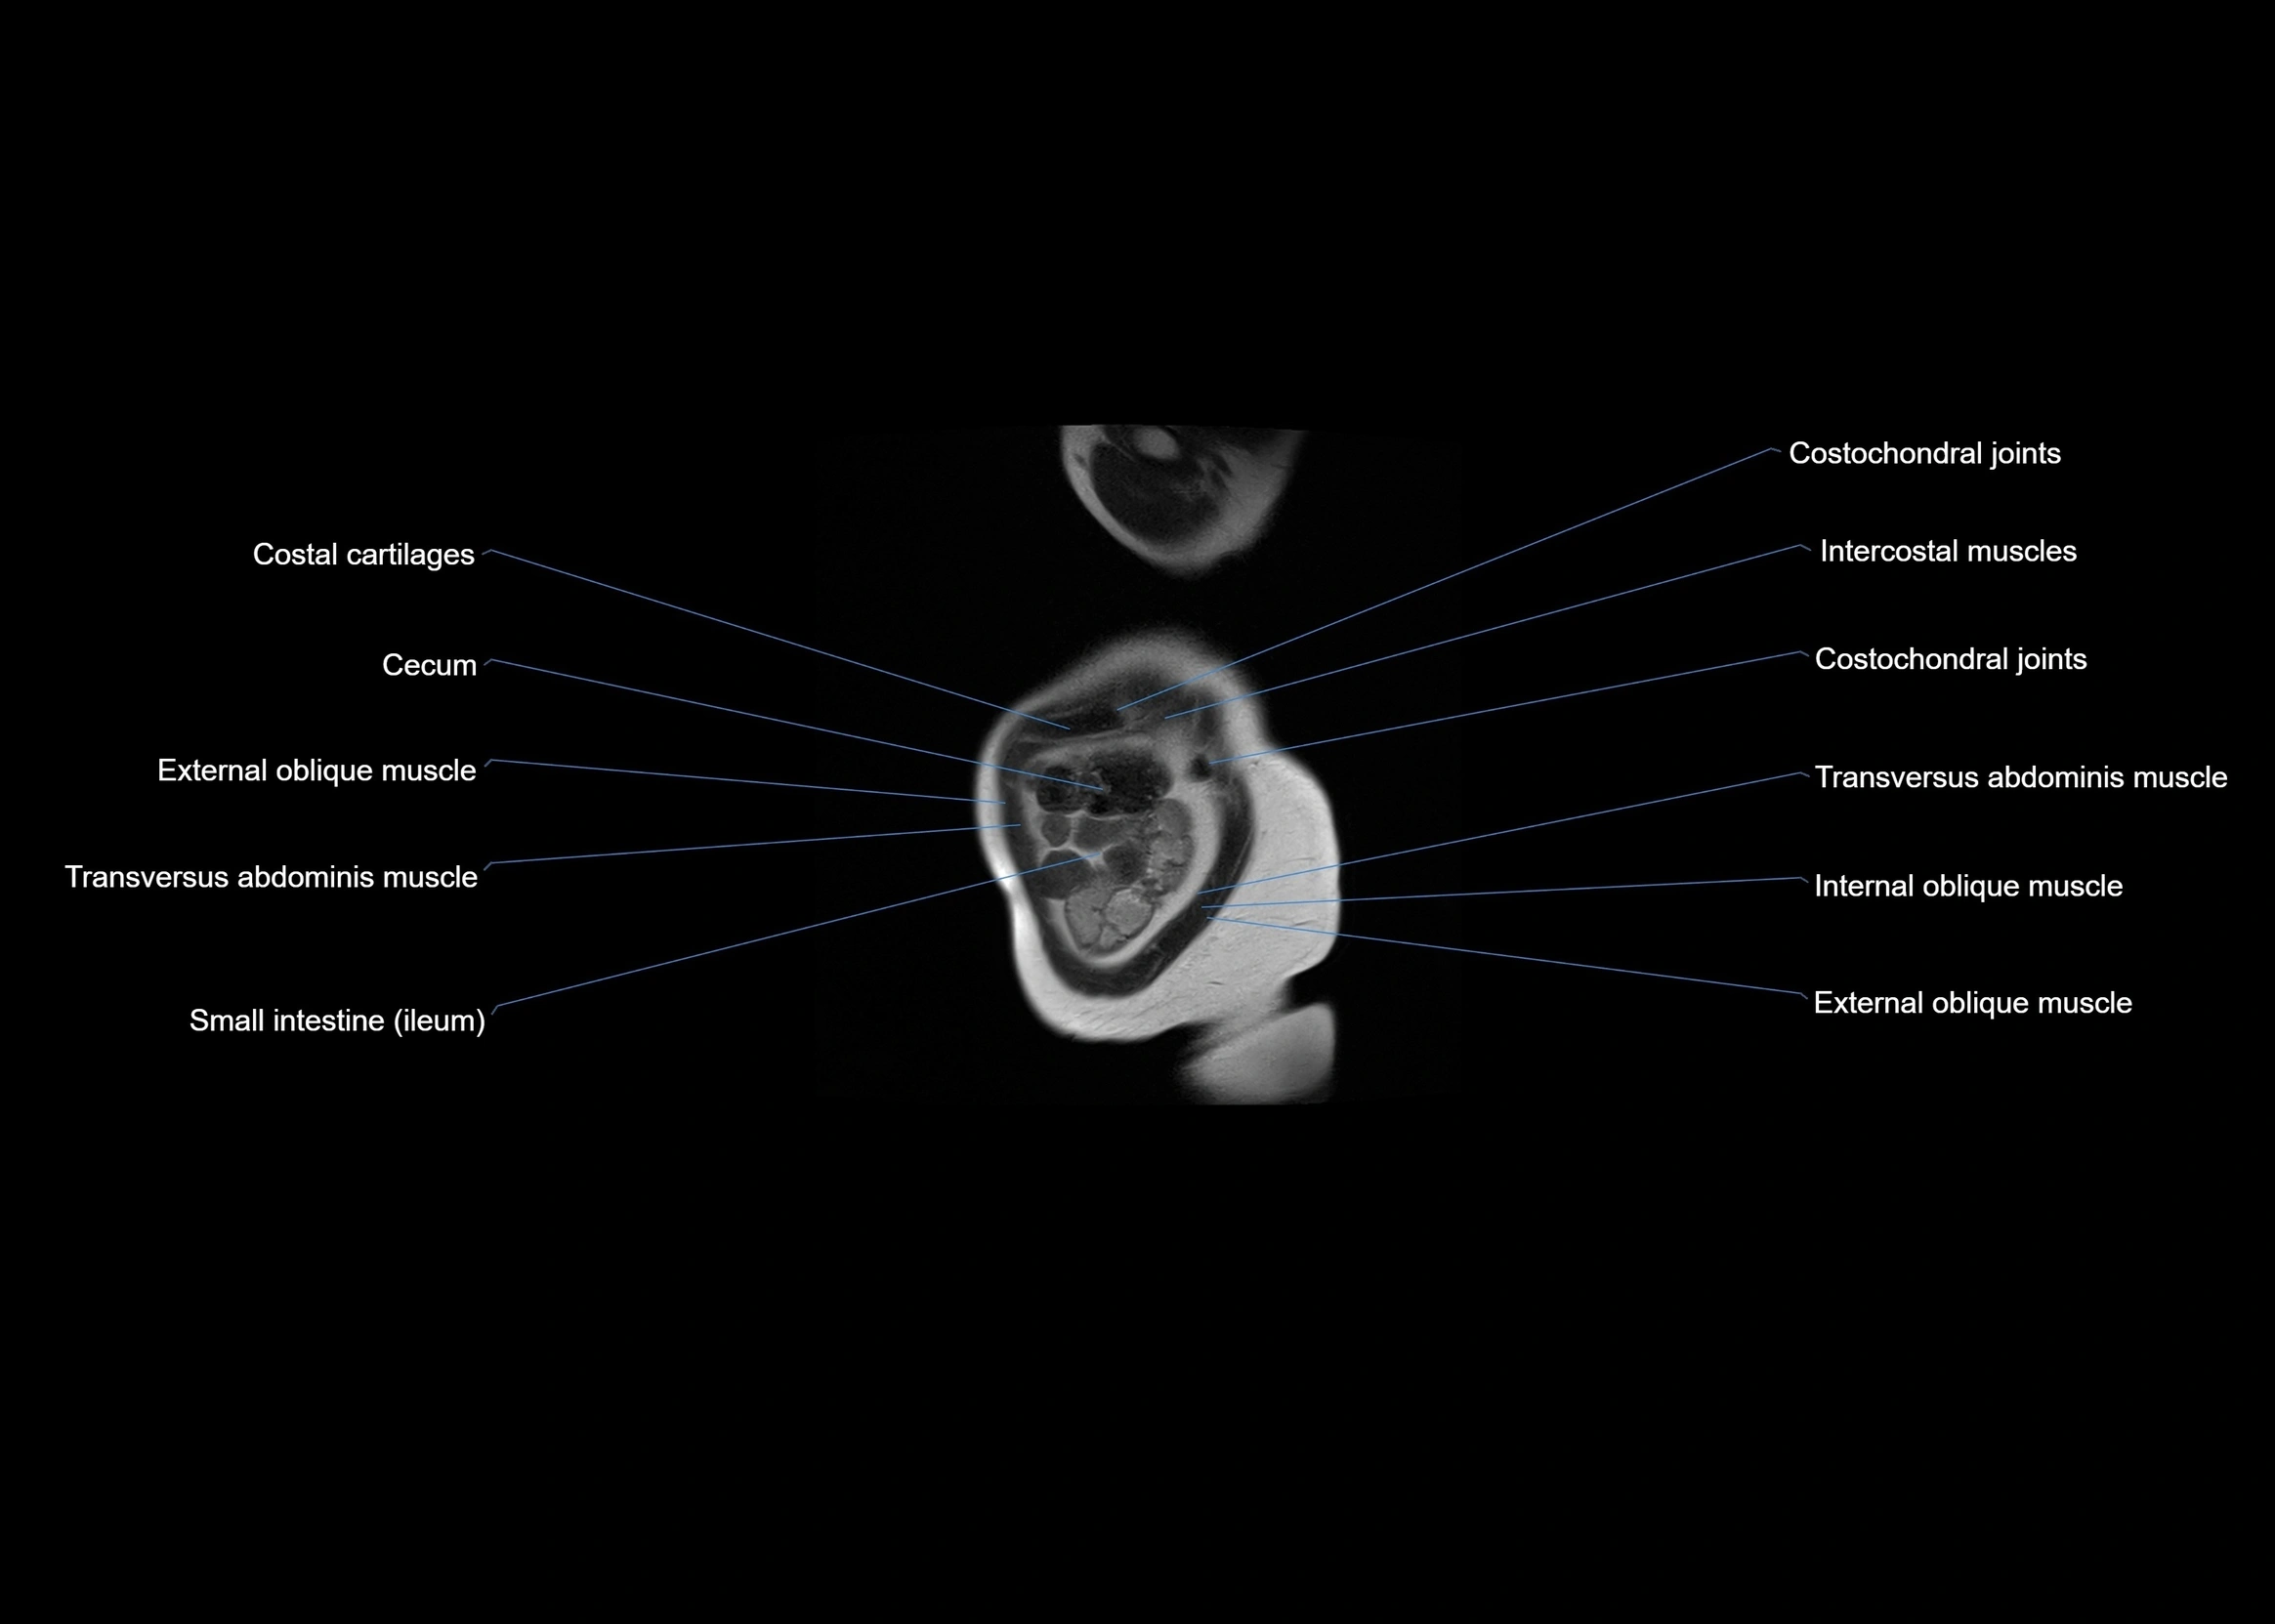

- Cecum

- Costochondral joints

- External oblique muscle

- Ileum

- Intercostal muscles

- Internal oblique muscle

- Transversus abdominis muscle